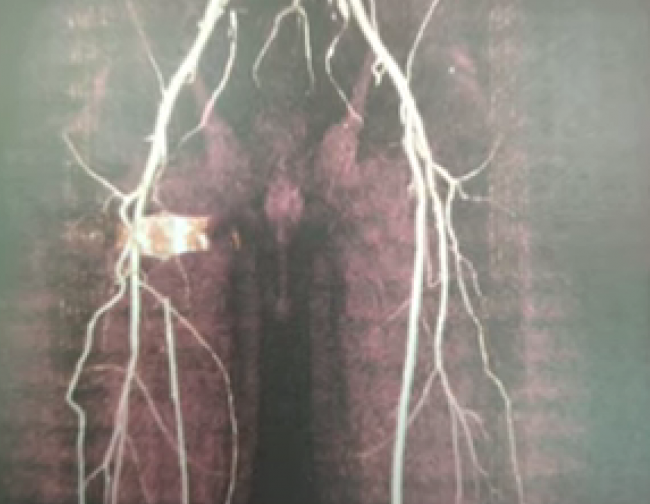

Однак після детального обстеження виявилось, що у нього в нозі знаходиться куля.

Виявилося, що куля знаходилася у самій артерії, тому й не було гематоми.